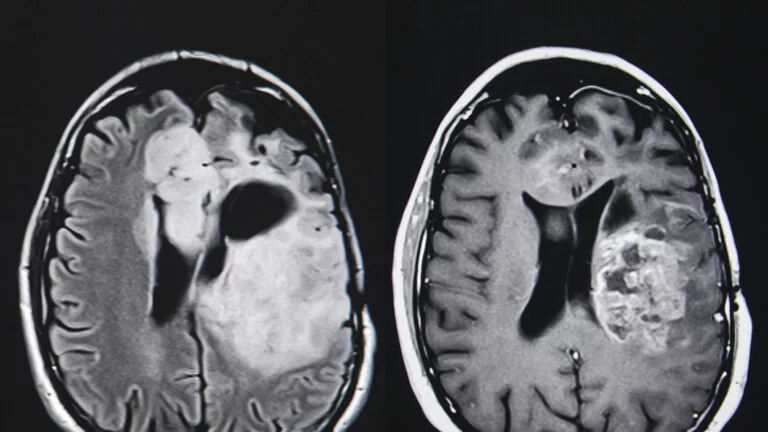

Glioblastoma, hızla büyüyen, bağışıklık tepkisini baskılayan ve beynin derinliklerinde ortaya çıkan kötü huylu bir tümördür. Şişlik, basınç ve kan akışını azaltarak dokulara zarar verir.